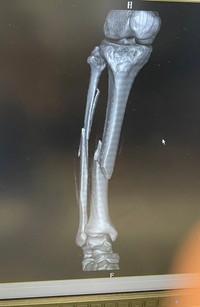

このつぶやきと共に、「合成か?!」と思うほどポッキリと折れた脚の骨のレントゲン写真が投稿されています。これはするさんが電動キックボードに乗って事故を起こし、怪我した時のものだといいます。

「こんな頑健な脚の形してるのにポッキリ折れて…」